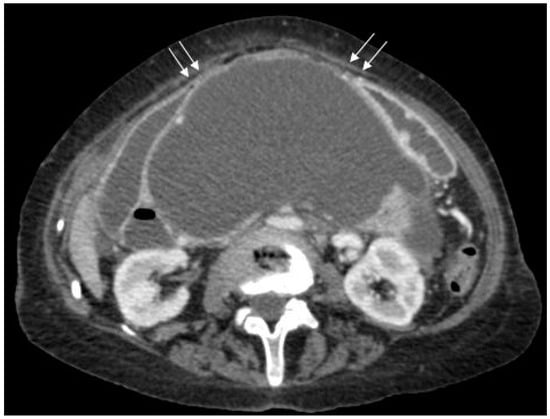

Figure 3.

Axial CT scan of the abdomen showing free air anterior to the liver (white arrows) and free fluid around the liver and spleen (black arrows).

Figure 4.

Axial CT scan of abdomen showing free air anterior to the liver (white arrows) and free fluid around the liver and spleen (black arrows).